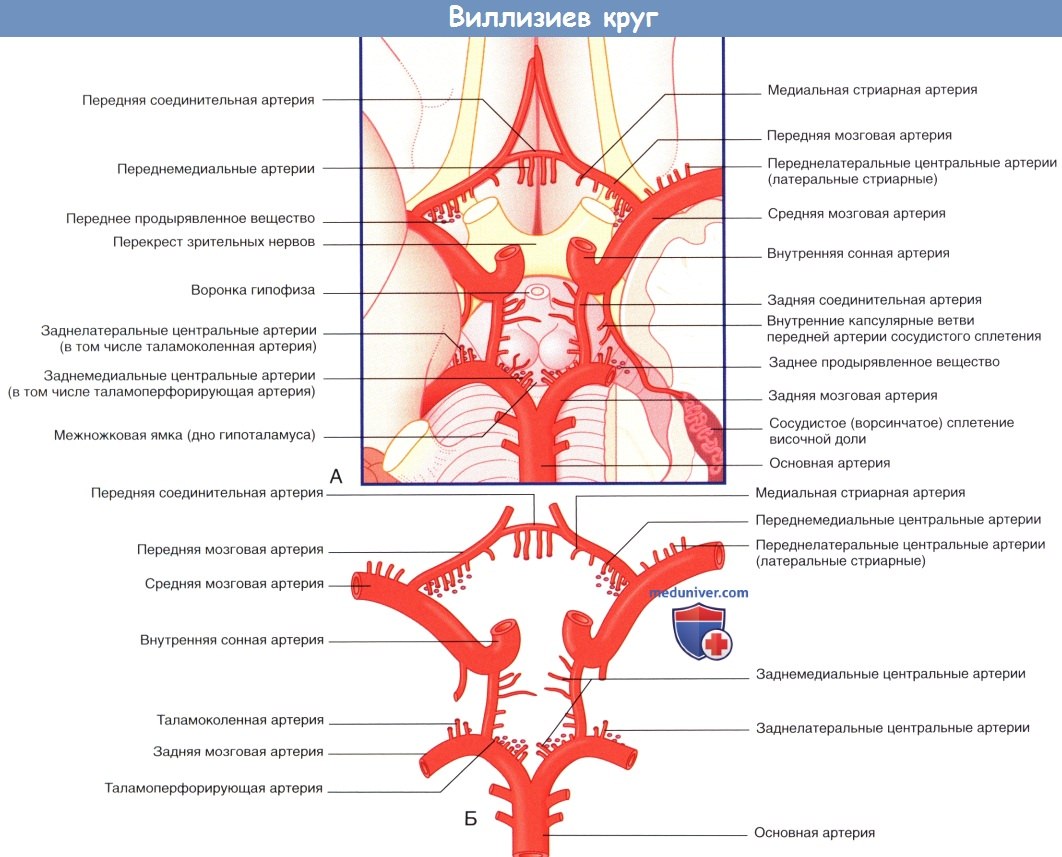

Необычные объекты: Переднее продырявленное вещество

Раздел: Альбом открытий